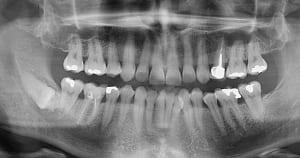

20-04-2021 Panoramique Début.JPG